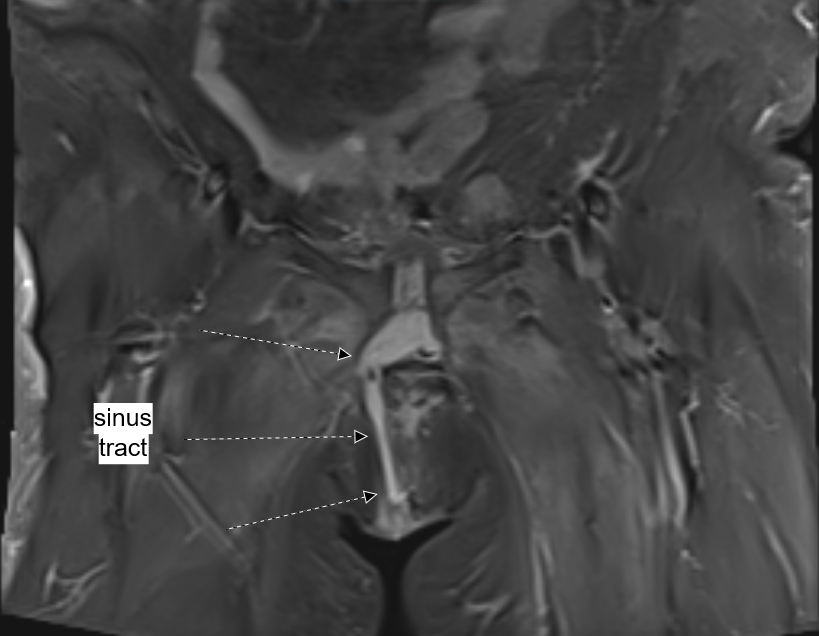

MRI of the pelvis was obtained and showed interval resolution of right vulvar abscess and persistent sinus tract extending from the skin at the level of the prior vulvar abscess extending into the pubic symphysis (Figure 3). Orthopedic surgery and infectious disease specialties were once again consulted for further recommendations and management. Per infectious disease recommendations, repeat blood and wound cultures were obtained. She then underwent additional surgical management by gynecology and orthopedics. Gynecology debrided the right vulvar skin, subcutaneous tissue and wound to the level of the pubic symphysis (Figure 4). Additionally, through an abdominal approach, orthopedic team p obtained access via a Pfannenstiel incision to evaluate the pubic symphysis and surrounding bone (Figure 5). The infected bone and surrounding tissue structures were thoroughly debrided and copiously irrigated, and wound was packed with 1g of vancomycin powder. Wound cultures obtained intra-operatively showed anti-microbial resistance to vancomycin, therefore per infectious disease recommendations, she was transitioned to daptomycin 10mg/kg every 24hrs and ceftaroline 600mg IV every 8 hrs. Ongoing wound care was provided with daily wet to dry dressing changes. Patient was discharged home in stable condition on post-operative day 6 and had daily home health visits for administration of IV antibiotics and wound care. She continued to be seen weekly in the ambulatory gynecology clinic. Her vulvar wound as well as abdominal incision showed progressively marked improvement and healing.

Figure 3 Coronal view of pelvic MRI showing sinus tract extending from skin of right vulvar abscess to the symphysis pubis.